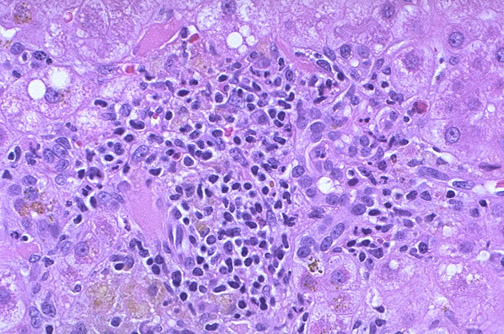

| At high magnification, a bile duct is being demolished by lymphocytes in this case of primary biliary cirrhosis (PBC). A characteristic laboratory finding with PBC is antimitochondrial antibody (AMA) in serum. Other findings in serum include: increased alkaline phosphatase, hypercholesterolemia, and hypergammaglobulinemia. Micronodular cirrhosis ensues. Jaundice is a late finding that suggests incipient liver failure. Patients sometimes have other autoimmune phenomena. |